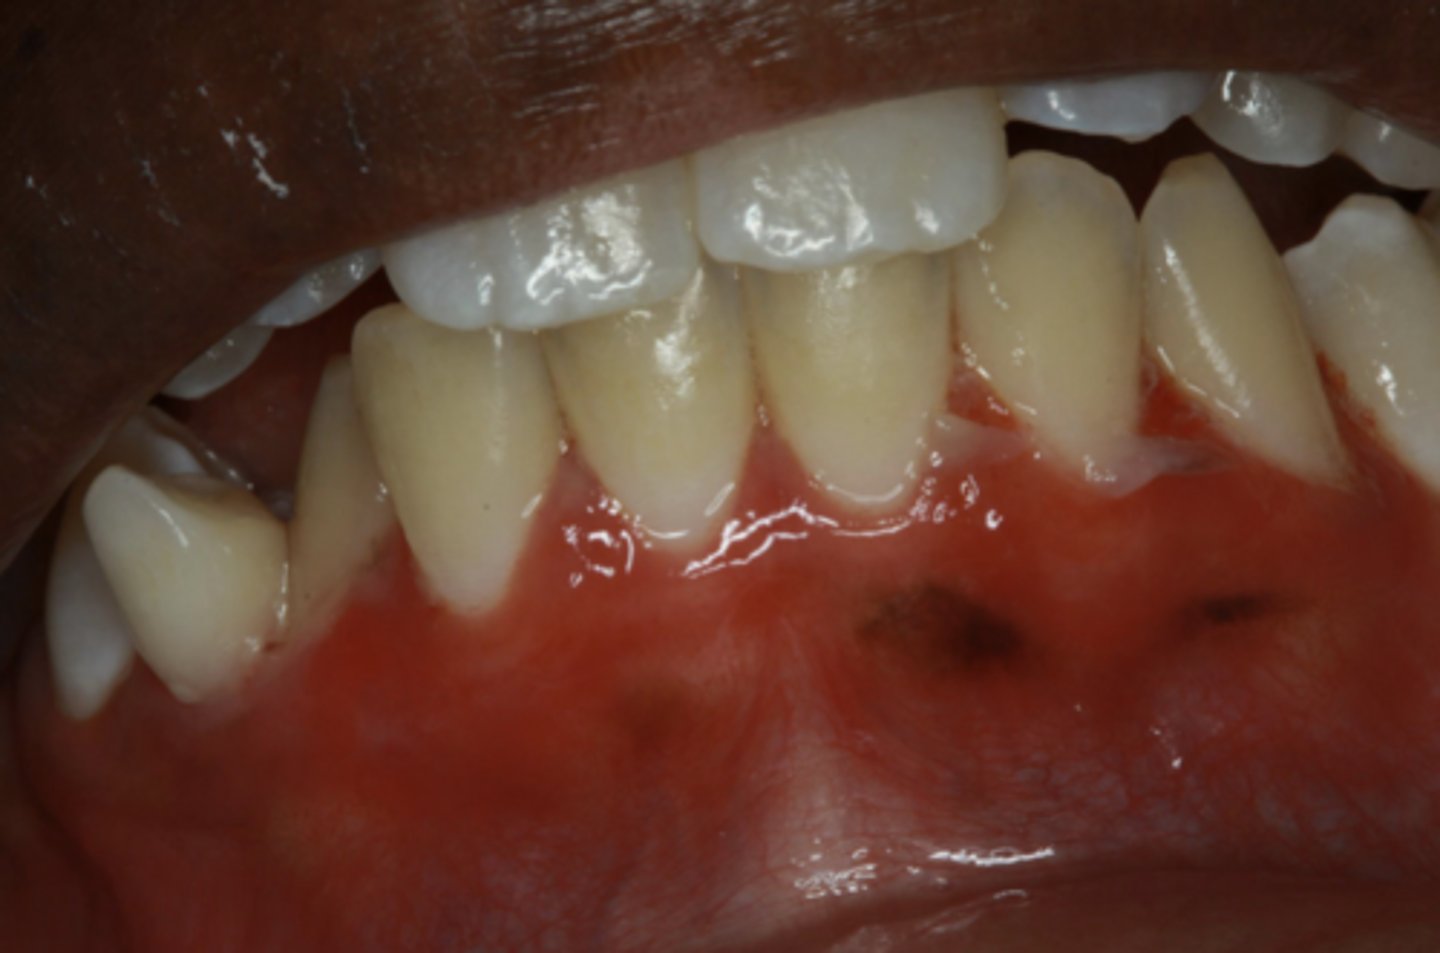

Chronic Cutaneous Lupus Erythematosus (CCLE)

These are clinical features of what condition?

- Scaly red patches on sun-exposed skin

- Oral lesions identical to lichen planus

- Rarely without skin lesions

Patient presents with these oral lesions but reports no other symptoms. Patient also has some hyperpigmented lesions on skin. What is the most likely differential?

These lesions are most likely caused by what condition?

- Oral lesions resemble lichen planus

- DIF shows IgM, IgG, and C3 in granular band at basement membrane

2 histopath features of Lupus Erythematosus